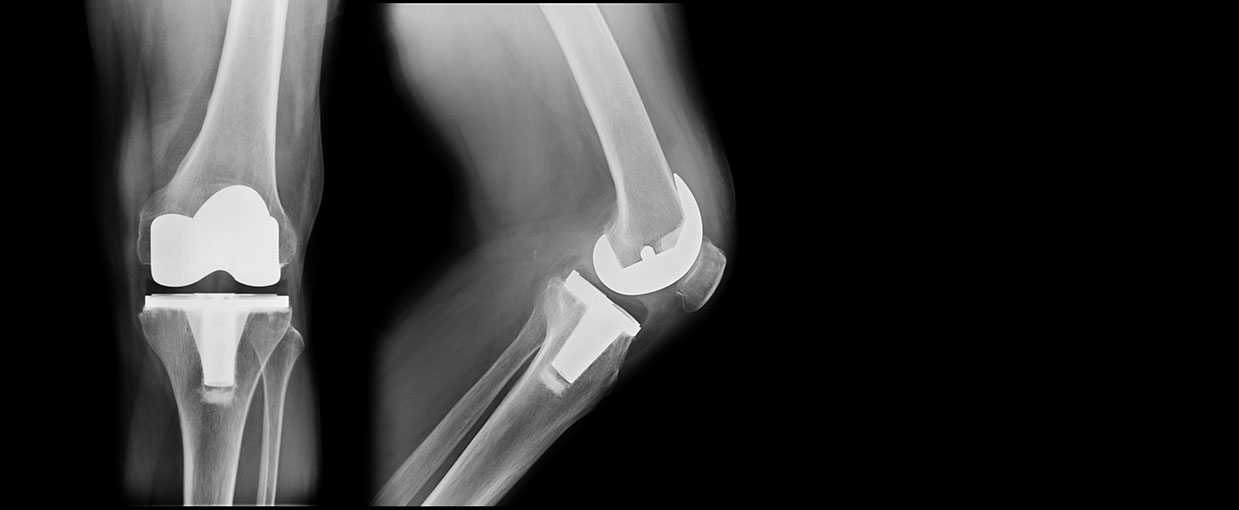

When that function is disrupted by injury or disease, knee replacement surgery may be recommended as a way to restore mobility and reduce pain. Sometimes referred to as knee arthroplasty or total knee replacement surgery, this procedure is one of the most successful in modern medicine. During surgery, any diseased or damaged parts of the knee joint are removed and replaced with artificial parts that imitate the natural movement of the knee. The most common reason for knee replacement surgery is to reduce the severe pain caused by osteoarthritis.

Total knee replacement surgery replaces the damaged parts of your knee with an artificial joint. It helps to relieve pain and restore function and mobility.

Partial knee replacement surgery is suitable when only one part of the knee joint is affected. It is often referred to as uni-compartmental surgery.

Revision knee replacement surgery replaces some or all of your original knee implants when they are no longer working effectively and causing pain.

Bilateral knee replacement surgery removes any damaged parts from both knee joints and replaces them with artificial implants. It can be performed simultaneously or as separate procedures.